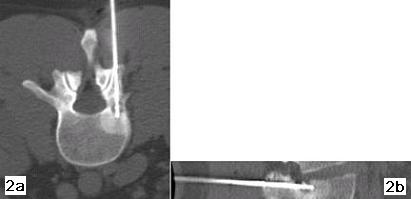

Figure 1a e 1b - La scansione TC sul piano trasversale (fig. 1a) e la ricostruzione su quello sagittale (fig. 1b) evidenziano la presenza di un piccolo osteoma osteoide del peduncolo Ds di L2 che aggetta nel forame di coniugazione.

Figure 2a e 2b - La scansione TC sul piano trasversale (fig. 2a) e la ricostruzione su quello sagittale (fig. 2b) dimostrano il corretto posizionamento dell'agoelettrodo (22G). Dopo 10 ore dalla termoablazione il paziente non ha più accusato il tipico dolore da osteoma osteoide.